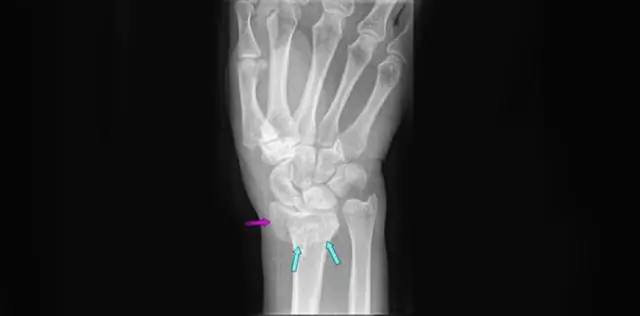

В радиус один из двух кости предплечья и находится на стороне большого пальца. Часть радиус, связанный с лучезапястным суставом, называется дистальным радиусом. Когда лучевые разрывы возле запястья, это называется перелом дистального отдела лучевой кости.

В радиус является большей из двух костей предплечья. Конец к запястью называется дистальный конец. Перелом дистальный радиус возникает, когда область радиус возле разрывов запястья. Дистальный радиус переломы очень распространены.